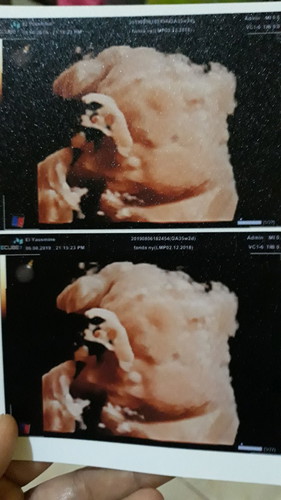

Hasil Usg

Assalamualaikum bunda2.... Ini hasil usg baby ku ukr 35w....,, anak ke 2 ku... Kmrn pas usg kta dr. Nya sudh siap lahir, bisa jd pertenghan ato akhir buln ini....,, Aku minta do'a nya sma bunda2 smua mudh2an perslinanku lancar shat ibu & baby nya...,,, & buat bunda2 smua mudh2an sllu di beri kshtan buat baby & ibu nya... Yg mau lahiran mudh2an di lancarkan smuannya ibu & baby nya shat jg...